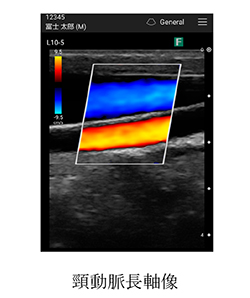

ポータブルエコー 観る透 超音波音速計・球状化率測定 ZX-5|ダコタ・ジャパンの詳細情報

超音波音速計・球状化率測定 ZX-5|ダコタ・ジャパン。超音波音速計・球状化率測定 ZX-5|ダコタ・ジャパン。HDX-9S 9型ワイドカラー液晶 GPSプロッター魚探 外付GPSアンテナ。ポータブルエコー 観る透アプリケーションをPCやタブレットにインストールし使用します。。ECHO (エコー) 50Vバッテリー ブロワ【BPB510】本体のみ — PLOW。※Apple製品は不可その他、付属品は全て揃っています。その他 wacom mobile studio pro